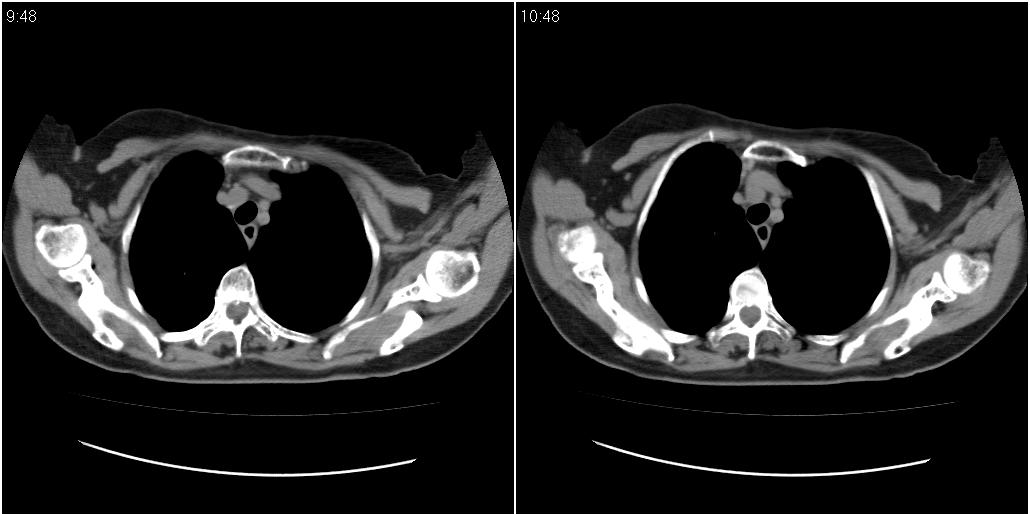

女性,72岁。去年9月份发现肺部病变,诊为肺结核并进行正规治疗至今,但复查后发现ct表现几乎没有变化。

右侧中叶支气管明显狭窄,建议行纤支镜检查!

右中间段支气管局限性狭窄,右中叶支气管亦稍显狭窄,但并未见明显占位表现,半年多了,无变化也许是好事,可能为炎性狭窄,建议继续随访。

右中叶炎性改变,支气管狭窄但较光滑,占位可能性不大。

右中间段支气管局限性狭窄,右中叶支气管亦稍显狭窄.